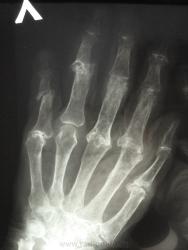

женщина,1930 г.р. , в наравлении -деформирующий артроз? В анализах повышено СОЭ, СРБ, ревмат. фактор.

Рентгенологически выделяют 4 стадии ревматоидного артрита: I стадия (начальная) — только околосуставной остеопороз; II стадия — остеопороз + сужение суставной щели; III стадия — остеопороз + сужение суставной щели + эрозии костей; IV стадия—сочетание признаков III стадии и анкилоза сустава. Раньше всего рентгенологические изменения при ревматоидном артрите появляются в суставах кистей и плюс-нефаланговых суставах.

Ревматологи с областной больницы ставят DS: Ревматоидный  артрит, акт. II. R-стадия III. НФС III. Вторичный ДОА III ст. Анемия хронических заболеваний.